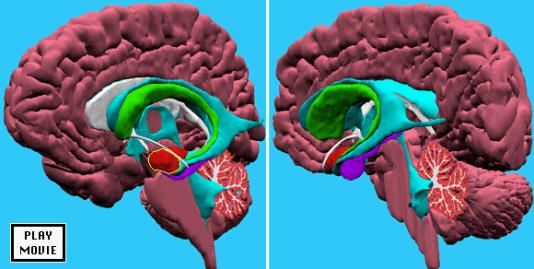

Emozione e gangli della base.

- Strutture nervose come i gangli della base potrebbero custodire gli schemi di emozioni ricorrenti.

La corteccia frontale entra in funzione quando vengono apprese nuove regole ed esperienze, e/o vengono scartate le precedenti, i gangli della base potenziano e richiamano regole ed esperienze precedenti basate su particolari contesti ambientali e storie di rinforzi.